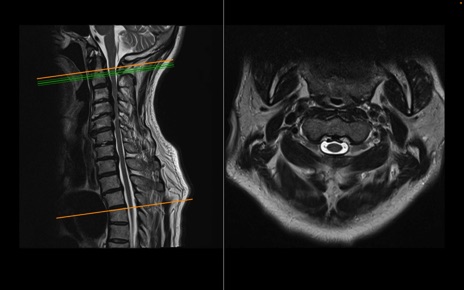

頚椎MRI

T2WI(横断像)

T2WI(矢状断像)